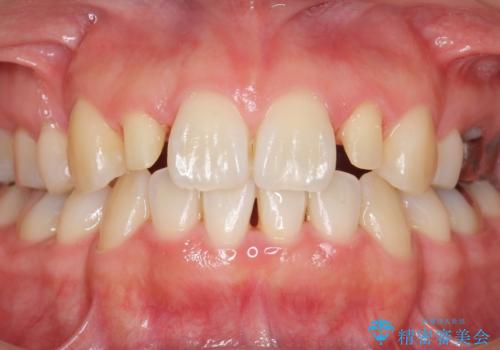

矮小歯 セラミッククラウンで綺麗に 30代女性

- 口元を綺麗にしたいとのご希望により来院された患者様です。

全顎的に歯並びにがたつきがあり、上の側切歯(上顎両側2)は生まれつき小さい歯(矮小歯)でした。

矯正治療後、矮小歯をセラミッククラウンにより理想的な歯の大きさに仕上げました。